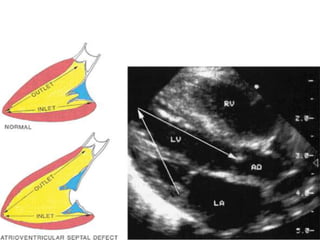

The complete AVSD

• This includes a primum ASD, but it is

contiguous with an inlet ventricular septal

defect (VSD).

• Common atrioventricular valve has a single

annulus.

• In partial AVSDs, incomplete fusion of the

superior and inferior endocardial cushions

results in a cleft in the midportion of the

anterior mitral leaflet, often associated with

mitral regurgitation.

• The primum atrial septal component of this

defect is usually large.